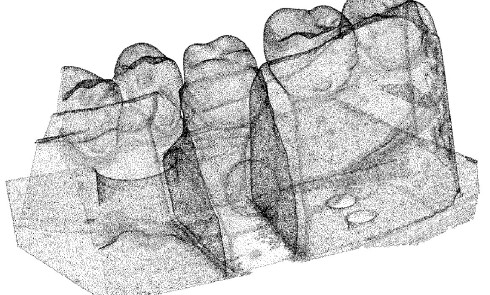

La pratique de la dentisterie numérique devient une part importante de l’activité de nombreux praticiens et laboratoires de prothèse (1)....La chaîne numérique en CFAO dentaire en prothèse conjointe

Les notions de chaîne numérique et de flux numériques sont fondamentales à la compréhension et à la maîtrise de la...Le rôle de l’assistante en prothèse fixée